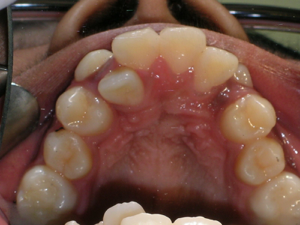

Here’s a young lady who presented with severe crowding. Often we think of crooked teeth as being limited to front teeth. Here one can see that back teeth can also get crowded. Braces were placed and select teeth were removed. Watch.